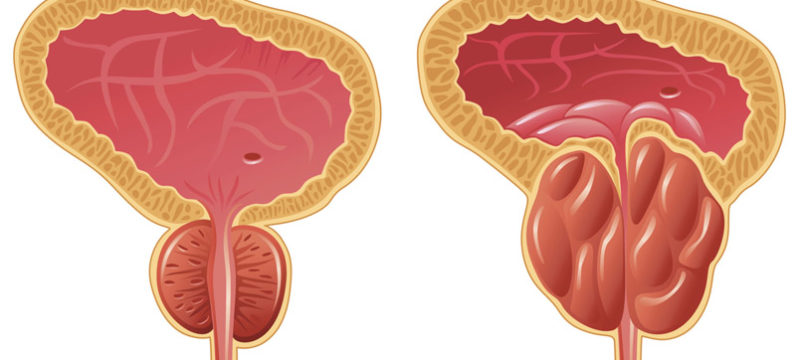

Η δαρολουταμίδη είναι αναστολέας υποδοχέων ανδρογόνου, χορηγούμενος από το στόμα και έλαβε έγκριση για τη θεραπεία ανδρών με μη μεταστατικό, ευνουχοάντοχοκαρκίνο του προστάτη (nmCRPC), οι οποίοι διατρέχουν υψηλό κίνδυνο ανάπτυξης μεταστατικής νόσου. Η έγκριση βασίστηκε στα δεδομένα από την μελέτη ARAMIS, μια μελέτη Φάσης ΙΙΙ που έδειξε εξαιρετικά σημαντική βελτίωση του διαστήματος επιβίωσης ελεύθερου μεταστάσεων […]